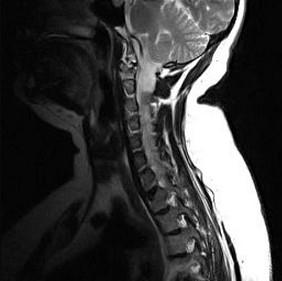

问题 关于椎管内肿瘤(如图所示)表现,下述哪项是错误的()

选项 A.髓内肿瘤常有排便功能障碍 B.髓内肿瘤感觉障碍常为自上向下发展 C.髓外硬膜下肿瘤可能有椎间孔扩大 D.圆锥肿瘤下肢有明显运动障碍 E.马尾肿瘤有剧烈神经根痛

答案 D